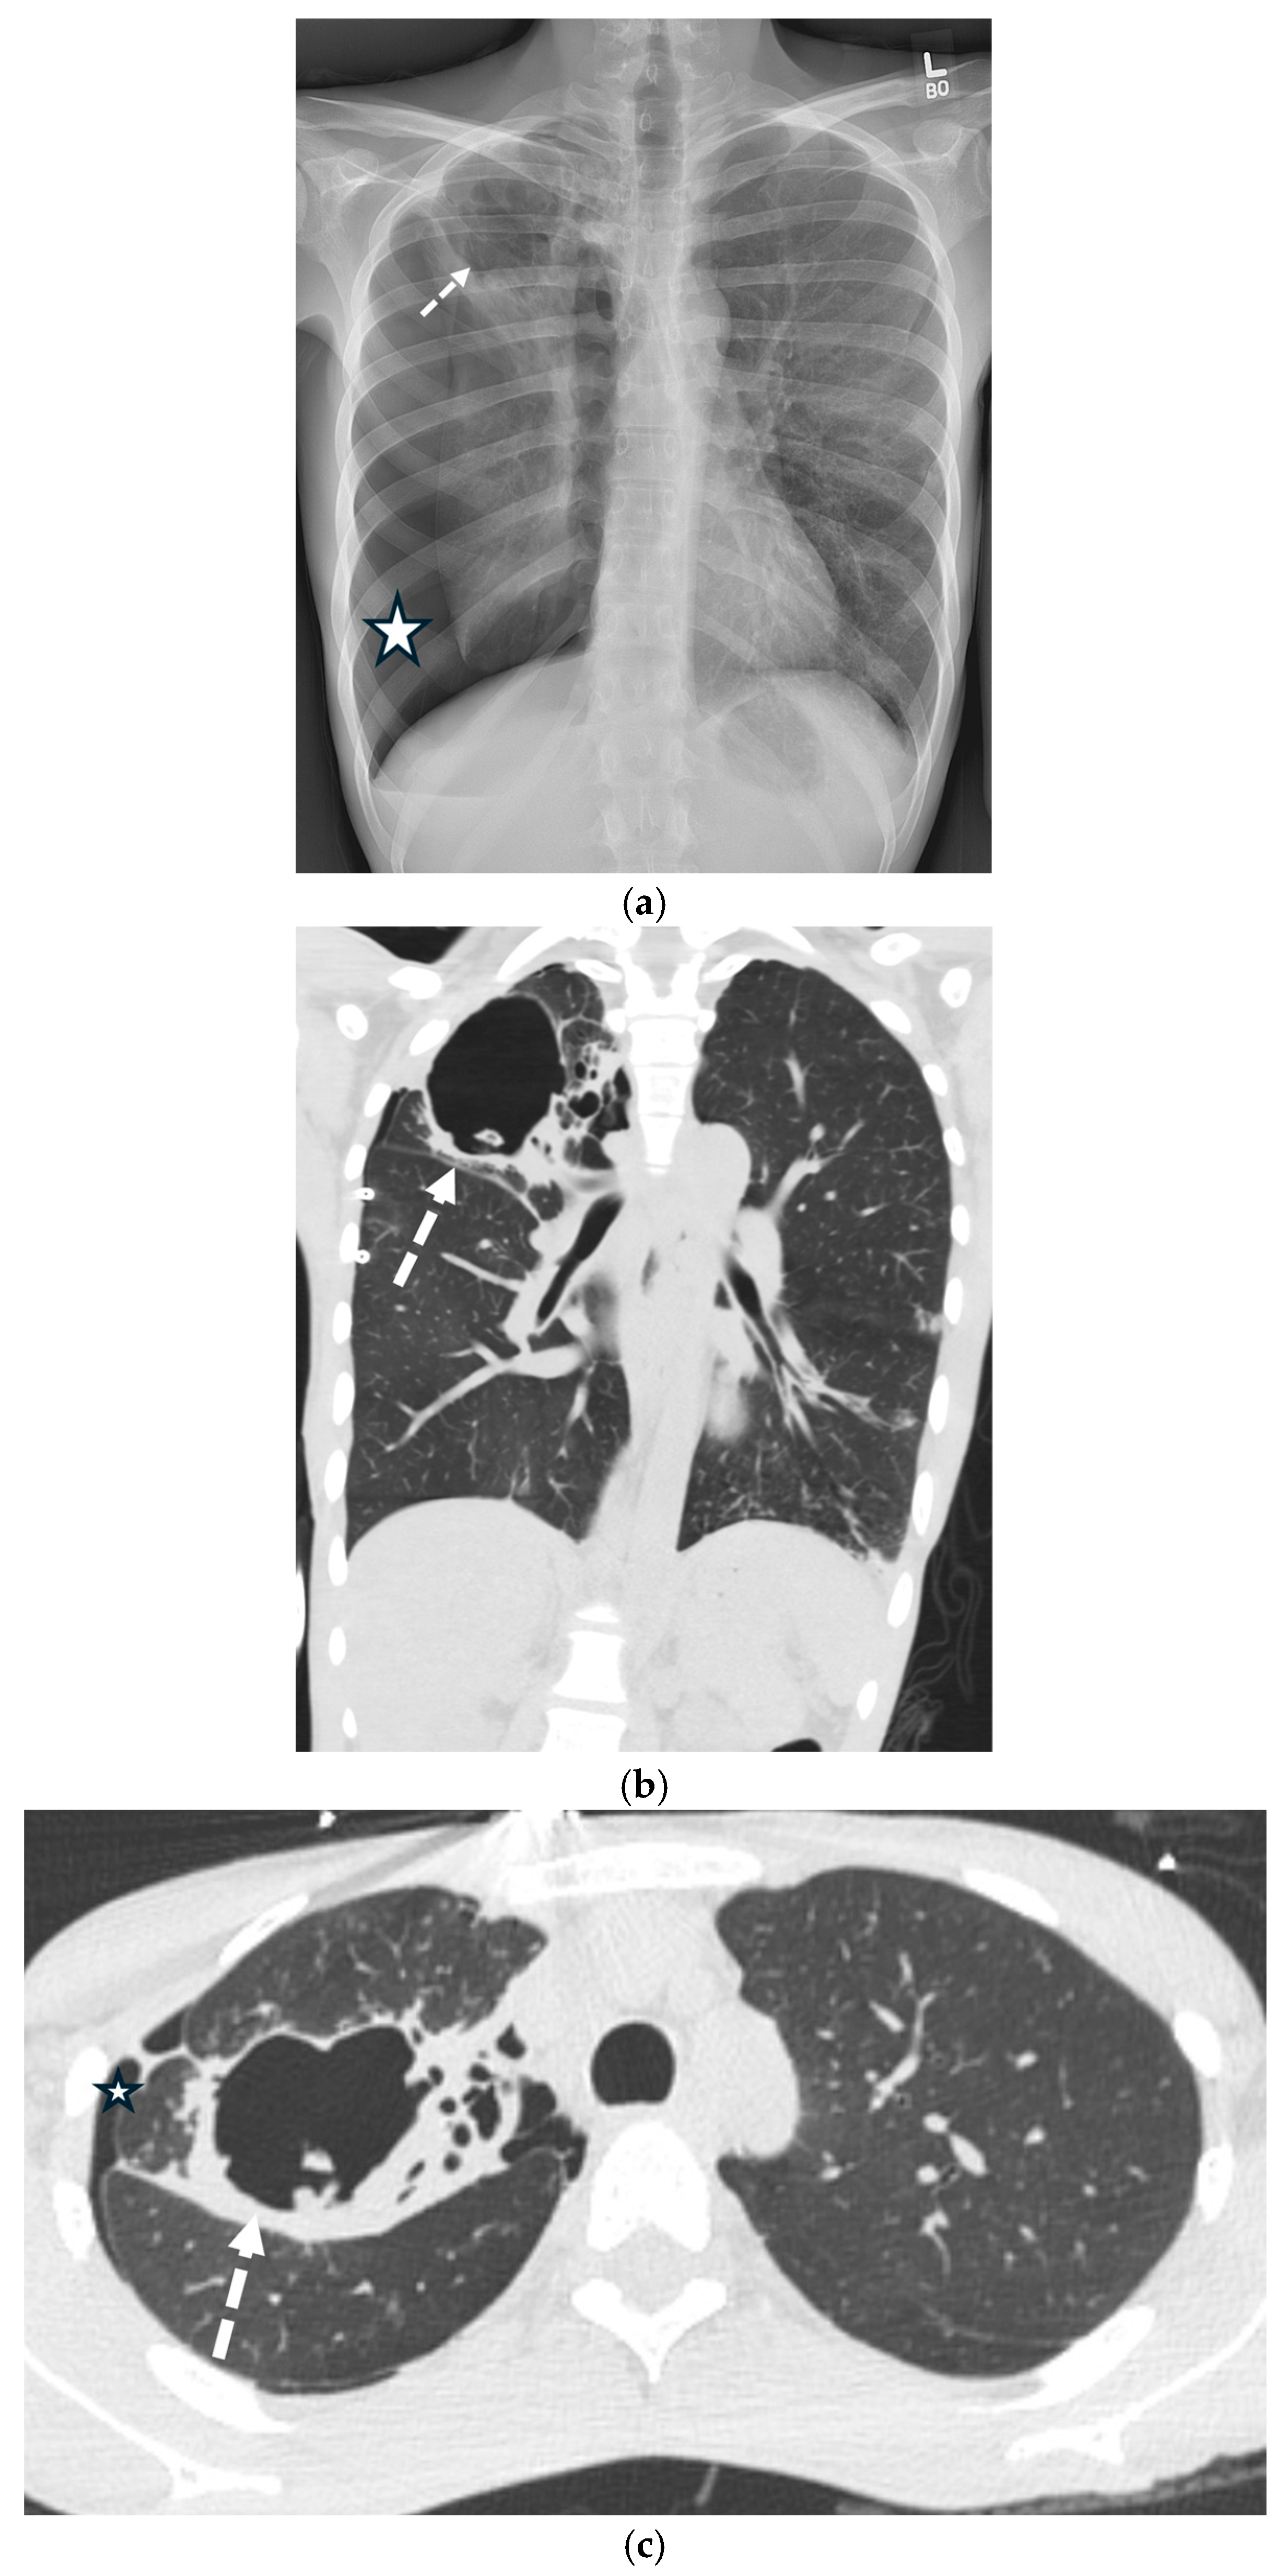

5.5.1. Pulmonary Langerhans Cell Histiocytosis (PLCH)

5.5.2. Lymphangioleiomyomatosis (LAM)

5.5.3. Birt–Hogg–Dubé Syndrome (BHDS)